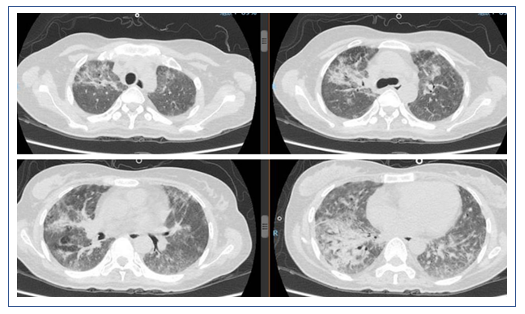

该患者急性起病,发热,痰中带血,病情较重,但影像学改变并不典型。患者胸部CT示双肺磨玻璃影,双下肺可以见与支气管伴行的肺血管明显增粗,右下肺可见血管影扩张,中叶胸膜下片状高密度影,左下肺血管影扩张较明显。目前在诊断方面考虑感染性病变和非感染性病变。非感染性病变主要考虑两类,一类是非肿瘤相关疾病,如自身免疫性疾病,另一类是肿瘤相关病变,如淋巴瘤、血液系统疾病等。结合患者的临床表现和检查结果,我个人认为非感染性疾病的可能性较大,仍需进一步检查明确,如支气管肺泡灌洗、肺活检等。

经过治疗后,该患者的氧合有所改善,胸部CT提示肺部磨玻璃影明显吸收,但斑片状实变影愈加明显。此外,还出现了少量的胸腔积液。所以还是考虑患者有无潜在的血管炎或结缔组织疾病。由于患者的血管病变比较突出,D-二聚体和肿瘤标志物水平升高。所以暂时不能除外淋巴瘤或血管相关肿瘤。此时可以考虑行支气管肺泡灌洗,同时取标本送病理检查。

该患者经过短期治疗后,肺部磨玻璃影明显吸收。这种效果应是来源于糖皮质激素的作用。除了血管炎是否也要考虑皮肌炎的可能,可以做皮肌炎抗体检查。另外,建议患者行支气管肺泡灌洗和NGS检查。患者胸部CT显示双下肺背段有斑片影,这或许与患者机械通气时间长有关,可能为重力依赖区斑片渗出影。

2019年1月16日复查胸部CT:双侧中下肺实变影较1月9日增多(图7)。

图7 患者复查胸部CT与前对比

左:2019年1月16日CT;右:2019年1月9日CT